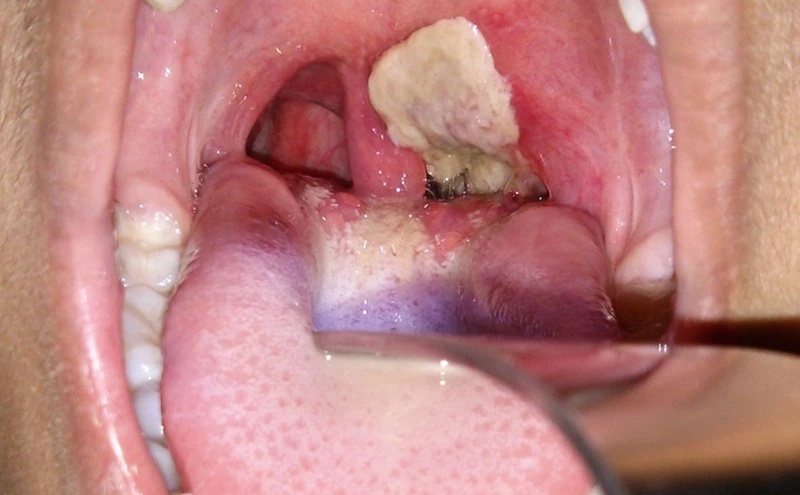

Giả mạc xuất hiện ở vùng hầu họng của người bệnh bạch hầu. Ảnh: The Museum of Health Care. |

Theo ông Tâm, bạch hầu là loại bệnh nhiễm trùng nhiễm độc, lây lan qua vi khuẩn. Bệnh lây lan nhanh, có khả năng nguy hiểm tính mạng nếu không phát hiện và điều trị kịp thời.